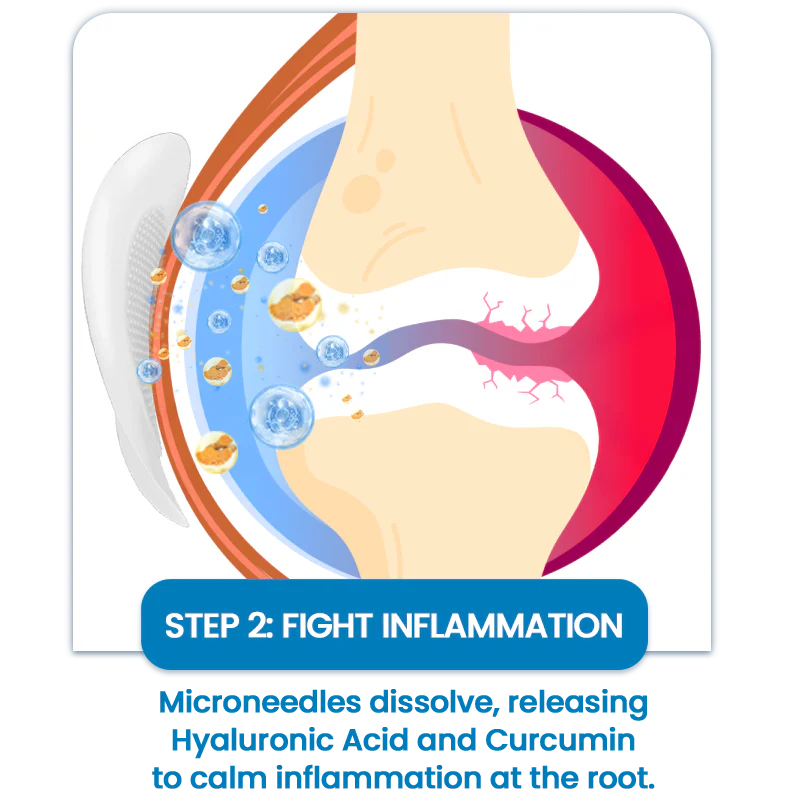

As the patch dissolves, the active ingredients penetrate the tissue — exactly where joint discomfort starts.

💧Hyaluronic Acid– Replenishes synovial fluid that cushions joints, literally “re-oiling” stiff movement

🌿Curcumin– Blocks inflammatory pathways causing swelling and morning stiffness

How It Works-Three-Step Joint Relief